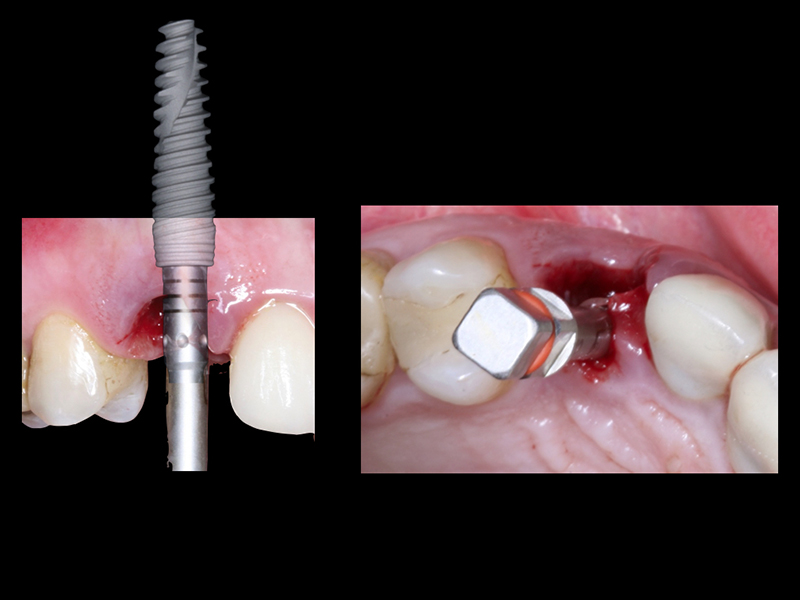

- Cirurgia de Instalação dos Implantes: Os implantes são fixados no osso maxilar ou mandibular, proporcionando uma base sólida para a prótese.

- Fixação da Prótese: Em até 72 horas após a cirurgia, a prótese provisória é instalada, permitindo que o paciente recupere a funcionalidade e a estética imediatamente.